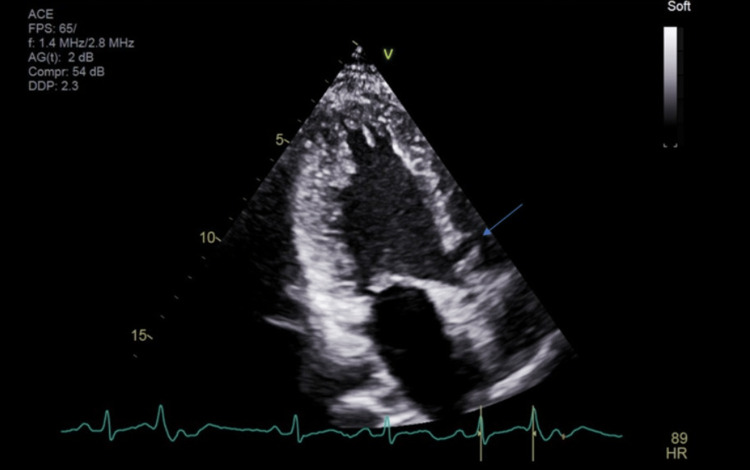

A cardiologist was consulted post echocardiography (Figures 2, 3). There was concern of cardiac arrest caused by ventricular tachycardia induced by prolonged QT interval and multiple PVCs. Unclear if long QTc was an acquired or congenital abnormality. She was transferred to a tertiary center for further workup. In the tertiary center coronary artery CT angiogram showed a calcium score of 0, pseudoaneurysm of membranous septum measuring 12mm x 7mm without any coronary anomalies which is a new finding from the CT angiogram. Cardiac MRI showed no infiltrative process, EF 52%, Qp: Qs 1.5, and subtle mid-wall enhancement of the basal septum. Electroencephalogram (EEG) was performed and possible seizure activity was ruled out. Electrophysiology study was significant for inducible PVCs localized to the free wall right ventricular outflow tract (RVOT), ablated successfully. The team implanted an implantable cardioverter-defibrillator (ICD). A repeat electrocardiogram (EKG) was performed (Figure 4). She was discharged with nadolol 40mg daily and advised against the usage of marijuana. Long QT syndrome genetic panel sent and result pending.